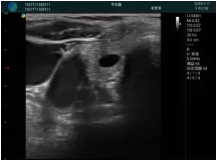

甲狀腺囊性結(jié)節(jié),囊壁鈣化,透聲好

甲狀腺囊性占位

M20查看:囊內(nèi)回聲均勻,邊界清晰,囊壁光滑

M20引導抽吸術(shù)后囊腫消失,原區(qū)域空腔形成,脂肪層與腺體層架構(gòu)發(fā)生改變